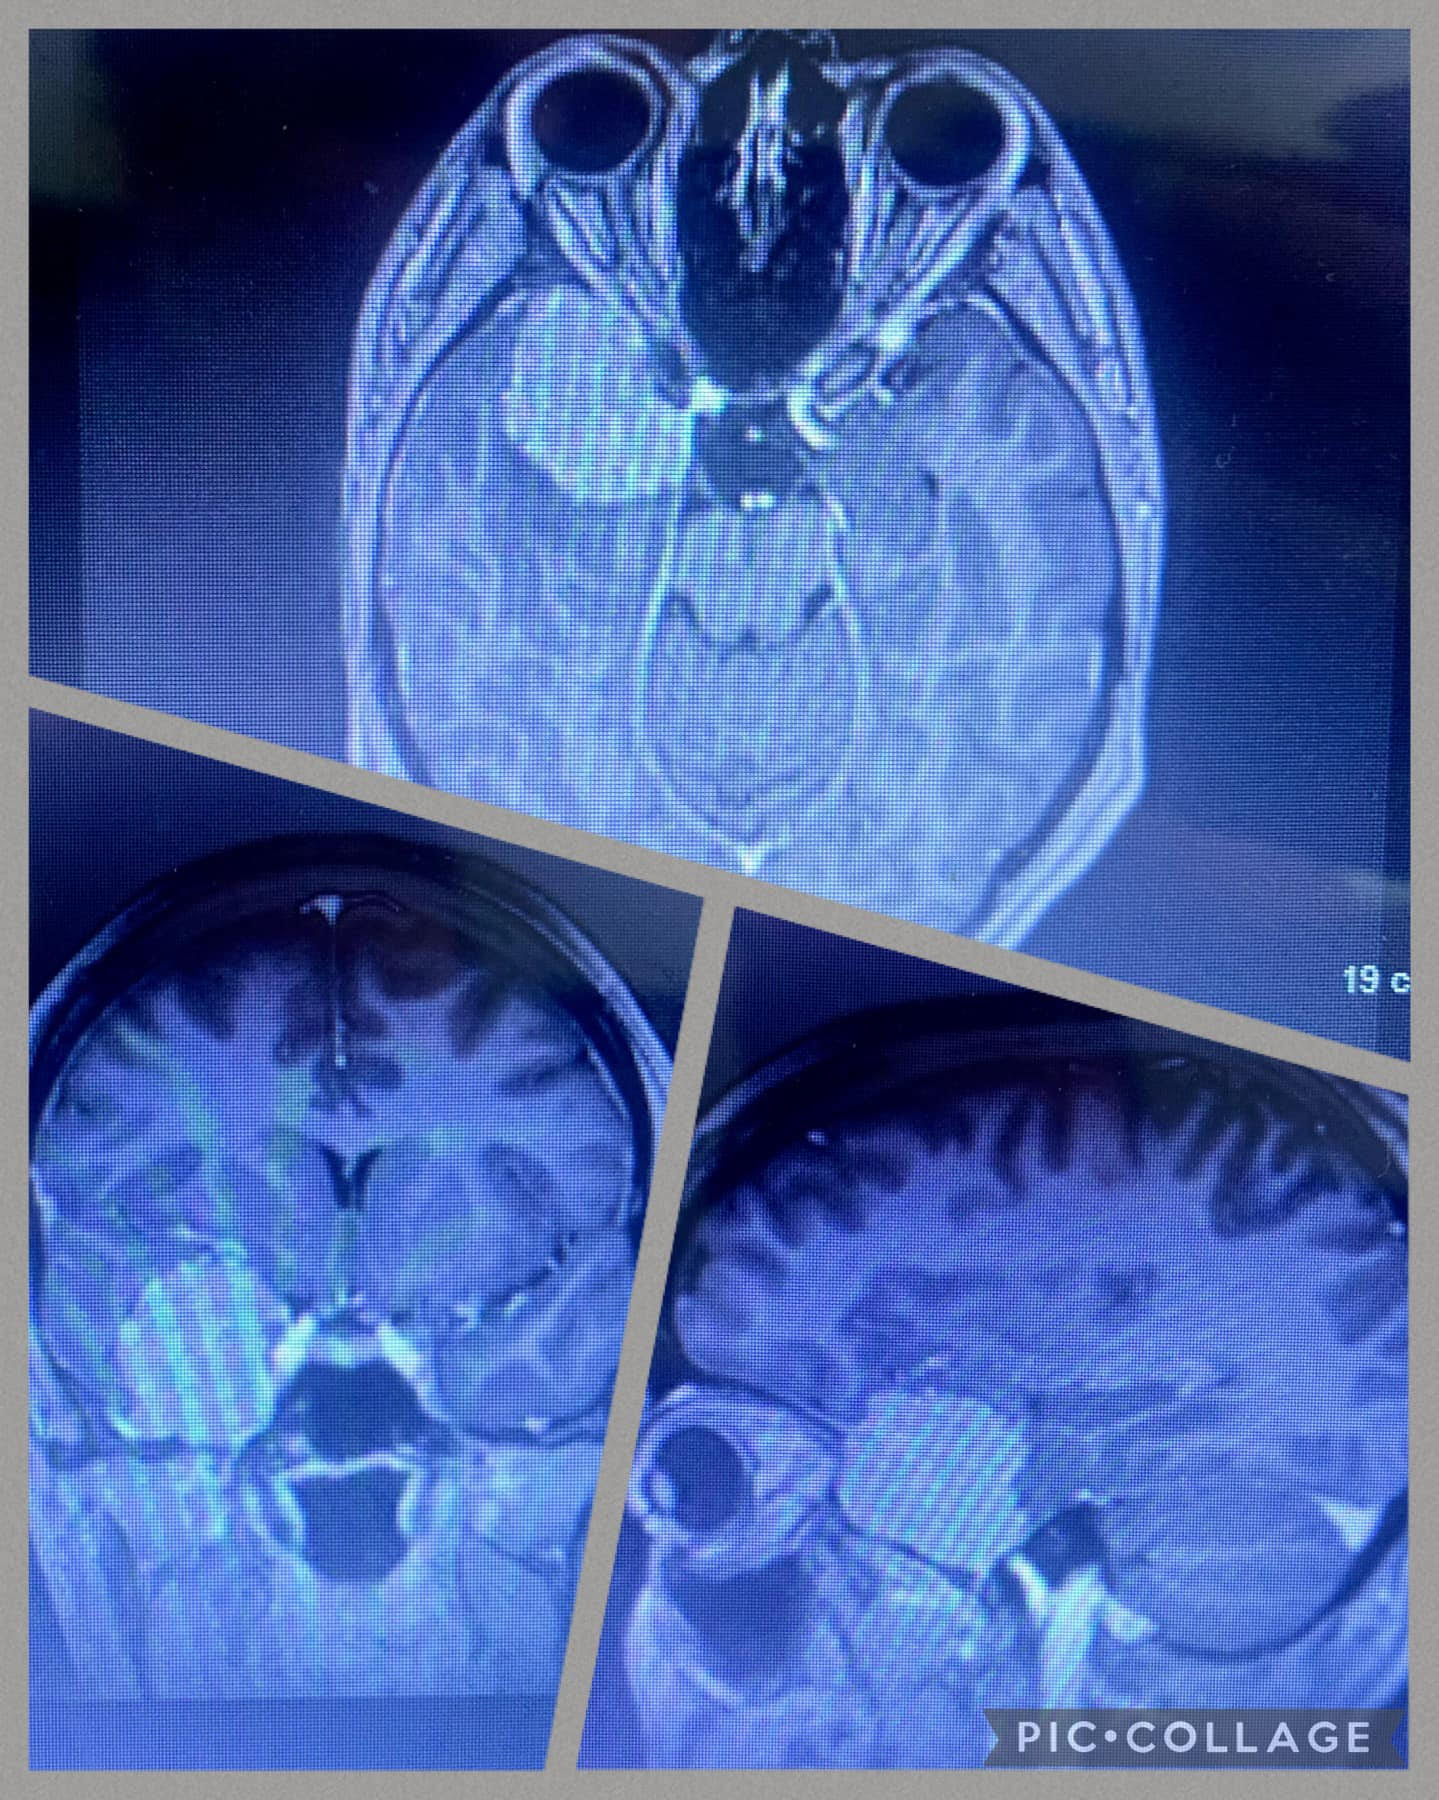

Rowan was taken in an ambulance to Leeds General, where she had an MRI scan in the early hours of Easter Sunday. Her surgeon began to describe the tumour to her – it was a three-to-four-centimetre diameter sphenoid wing meningioma, and it was pushing on her right optic nerve. There was no discussion of needing to watch and wait, the surgeon asserted they would be taking it out.